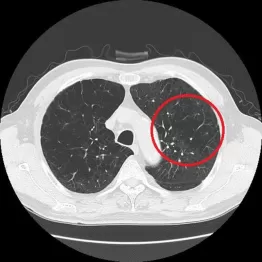

この点、前出の茂木理事長も、「COPDの発症と最も関連があるのは、たばこと考えて間違いないでしょう。たばこを長期にわたって吸っているうちに症状が進むと空気の通り道だけではなく、その先端の肺胞が壊れて穴が開きます。これがいわゆる『肺気腫』で、こうなると酸素と二酸化炭素の交換がうまくできずに息切れがひどくなり、最悪、常に酸素ボンベを持ち歩かなくてはならなくなるなど普通の生活が送れなくなってしまうのです」とその弊害を認める。